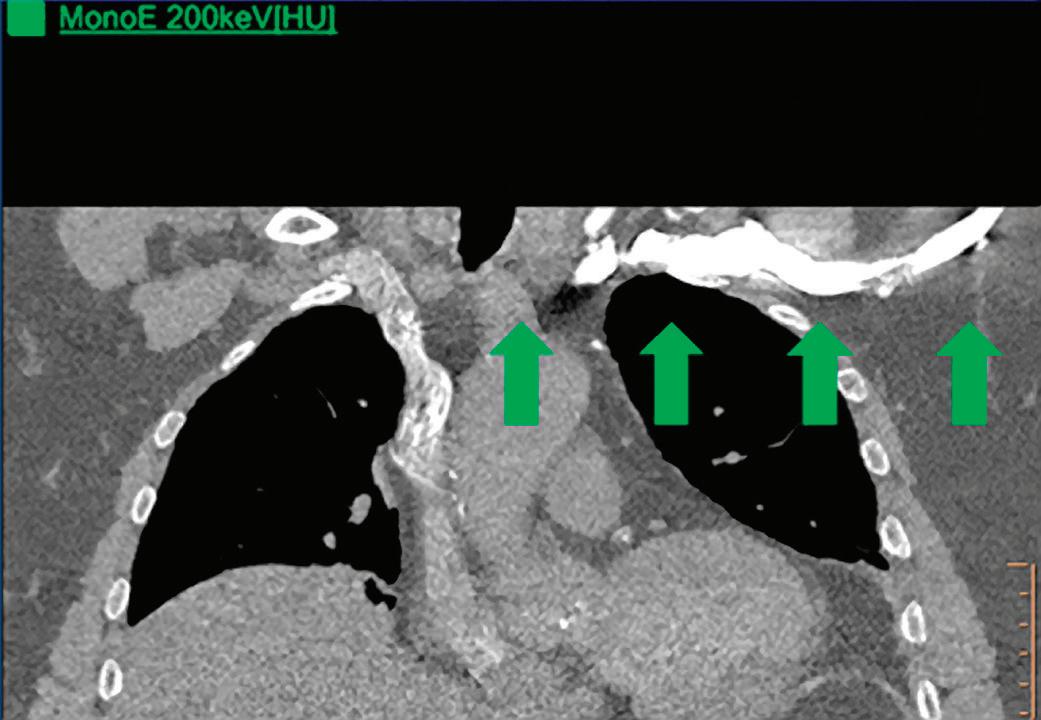

CT breath-hold results in a poor enhancement of the pulmonary arteries on the displays from left to right: monoenergetic 70 keV, monoenergetic 55 keV, monoenergetic 40 keV, and Z effective map showing a perfusion deficit of the lung parenchyma (white arrow). When decreasing the energy, the iodine attenuation is progressively boosted and reveals the presence of a thrombus (colored arrows) in a sub-segmental pulmonary artery corresponding to the territory of the perfusion deficit. (c) Monoenergetic 200 keV reduces beam hardening from dense contrast medium compared to conventional CT images.

Once the pair (αp, αc) is calculated for every voxel, and since fp(E) and fc(E) are known functions of energy, one may synthesize monochromatic images at different energies. These images can be used for routine diagnosis similar to conventional images. With a single scan at 120 kVp (or 140 kVp for obese patients), a dual-layer spectral CT acquisition allows the reconstruction of virtual monochromatic images from 40 keV up to 200 keV, in increments of 1 keV. The minimum of 40 keV was chosen in order to stay above the k-edge of the most common materials including iodine (iodine k-edge = 33 keV). If the scan is performed at 120 kVp, the conventional CT images of a typical-size patient will display an attenuation corresponding to the average of the X-ray spectrum (˜70 keV in a body scan) but with beam hardening artifacts from dense structures (like bones) which are due to the polychromatic nature of the X-ray beam. Since the photoelectric effect is dominant at lower keV, and is relatively high for high Z materials, low keV imaging (below 70 keV for body) can be used to enhance the absorption of high Z material such as iodine (Z=53), compared to the conventional CT images.15,16 This can be of particular interest to enhance the iodine uptake for patients with renal dysfunction, where the total injected volume of iodinated contrast medium is very limited. This attenuation boost can also be very useful in the case of a missed injection (Figure 2a and b). Compton scattering on the other hand is dominant at higher keVs and does not exhibit a strong relationship with Z. High keV imaging will then be of particular interest to minimize the absorption of high Z materials and minimize all types of associated artifacts (metal beam hardening from metal implants, beam hardening from dense contrast medium, blooming of stents or calcium, etc.) (Figure 2c).17,18,19